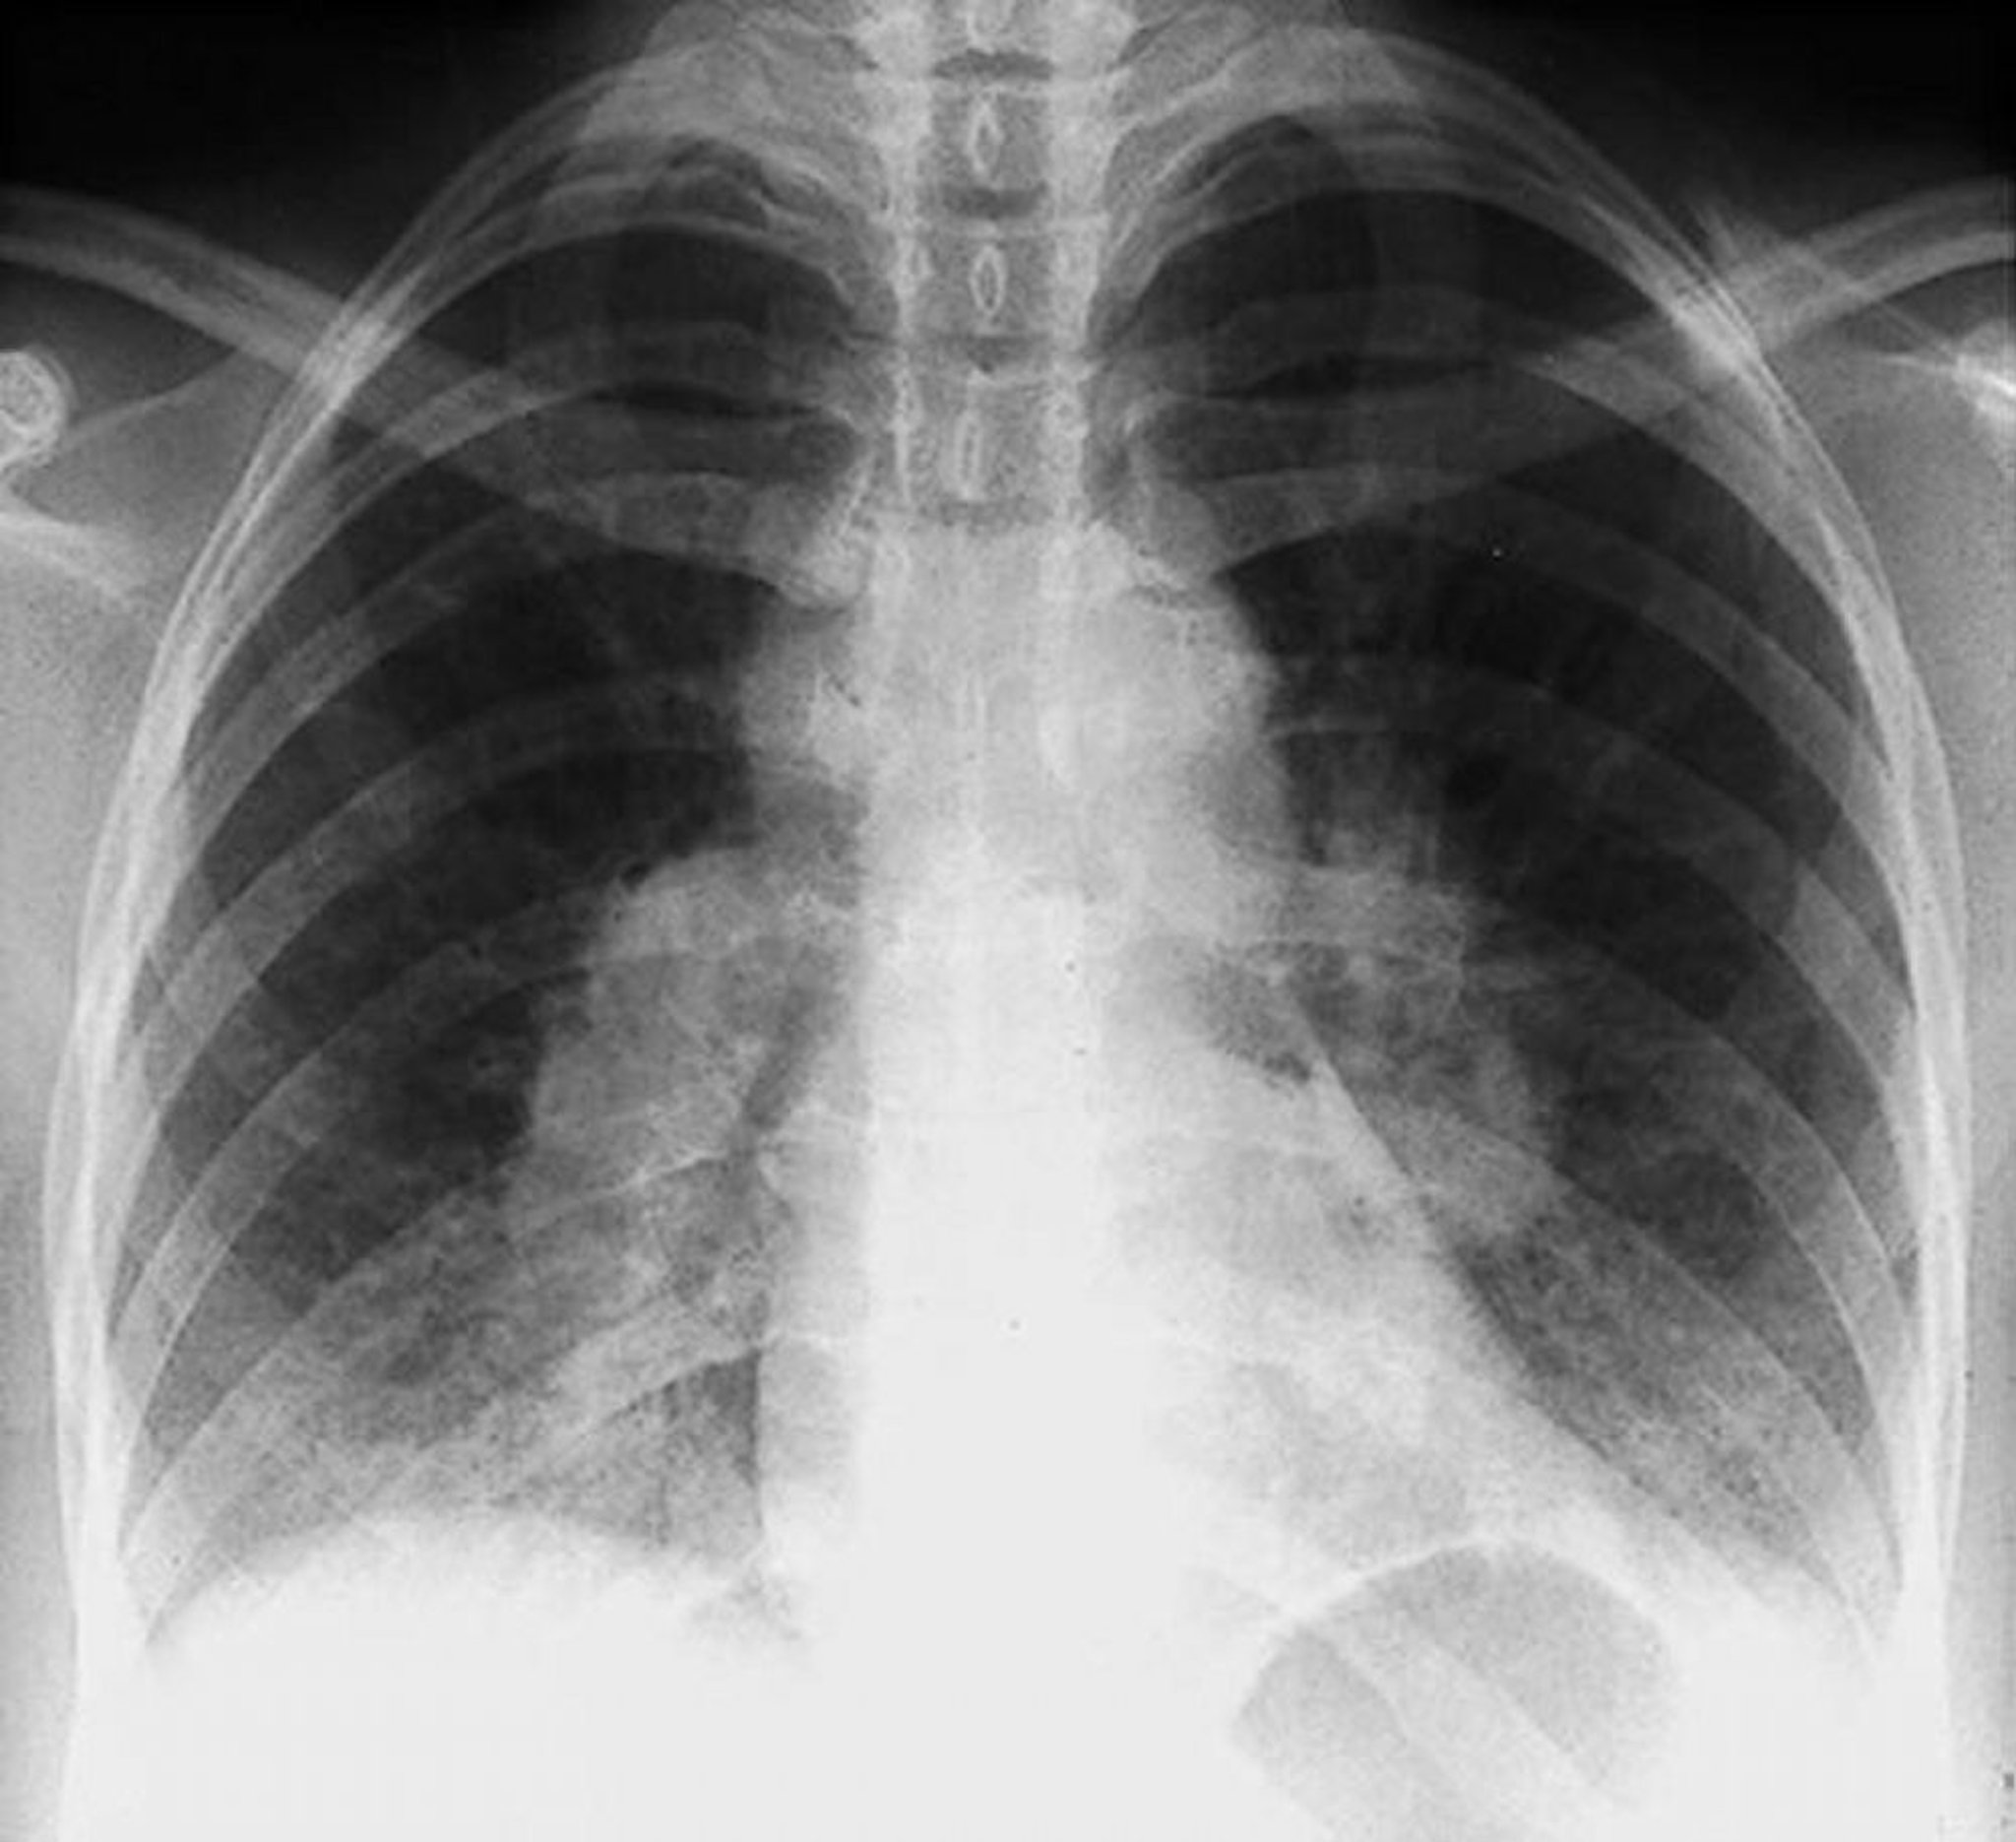

Саркоидоз — стадия I

Двухсторонний прикорневой лимфаденит при I стадии саркоидоза.

By permission of the publisher. Из Tanoue L, Elias J. In Bone's Atlas of Pulmonary and Critical Care Medicine. Edited by J Crapo. Philadelphia, Current Medicine, 2005.